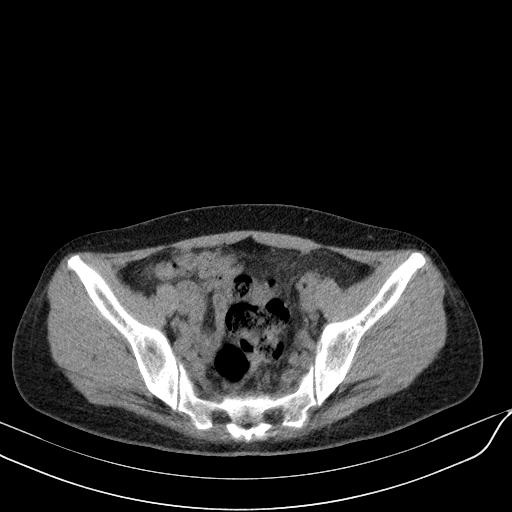

标题: CT23965:无外伤史,下腹痛 [打印本页]

标题: CT23965:无外伤史,下腹痛

肠道未准备,继续往下扫,乙状结肠占位不排除。建议钡灌或结肠镜检查。

乙状结肠占位不排除

扫描时应做肠道准备,口服稀释造影剂。

肠道肿瘤,建议行钡剂灌肠检查。